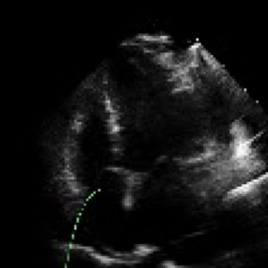

Accurate and consistent predictions of echocardiography parameters are important for cardiovascular diagnosis and treatment. In particular, segmentations of the left ventricle can be used to derive ventricular volume, ejection fraction (EF) and other relevant measurements. In this paper we propose a new automated method called EchoGraphs for predicting ejection fraction and segmenting the left ventricle by detecting anatomical keypoints. Models for direct coordinate regression based on Graph Convolutional Networks (GCNs) are used to detect the keypoints. GCNs can learn to represent the cardiac shape based on local appearance of each keypoint, as well as global spatial and temporal structures of all keypoints combined. We evaluate our EchoGraphs model on the EchoNet benchmark dataset. Compared to semantic segmentation, GCNs show accurate segmentation and improvements in robustness and inference runtime. EF is computed simultaneously to segmentations and our method also obtains state-of-the-art ejection fraction estimation. Source code is available online: https://github.com/guybenyosef/EchoGraphs.

翻译:对回声心电图参数的准确和一致预测对于心血管诊断和治疗十分重要,特别是左心室的分块可用于产生心血管体积、弹出分数(EF)和其他相关测量结果。在本文件中,我们提出一种新的自动化方法,称为EchoGraphs,用于预测弹出分数,并通过探测解剖关键点对左心室进行分解。根据图表变异网络(GCNs)进行直接协调回归模型用于检测关键点。GCNs可以学习根据每个关键点的局部外观以及所有关键点的全球空间和时间结构来代表心脏形状。我们在EchoNet基准数据集上对EchoGraphs模型进行了评估。与语系分化相比,GCNs显示了准确的分化和稳健度和推断运行时间的改进。EF是同时计算分解的,我们的方法也获得了最新化的弹射分数估计。源代码可在线查阅:https://github.com/guybenyos/Echophophs。